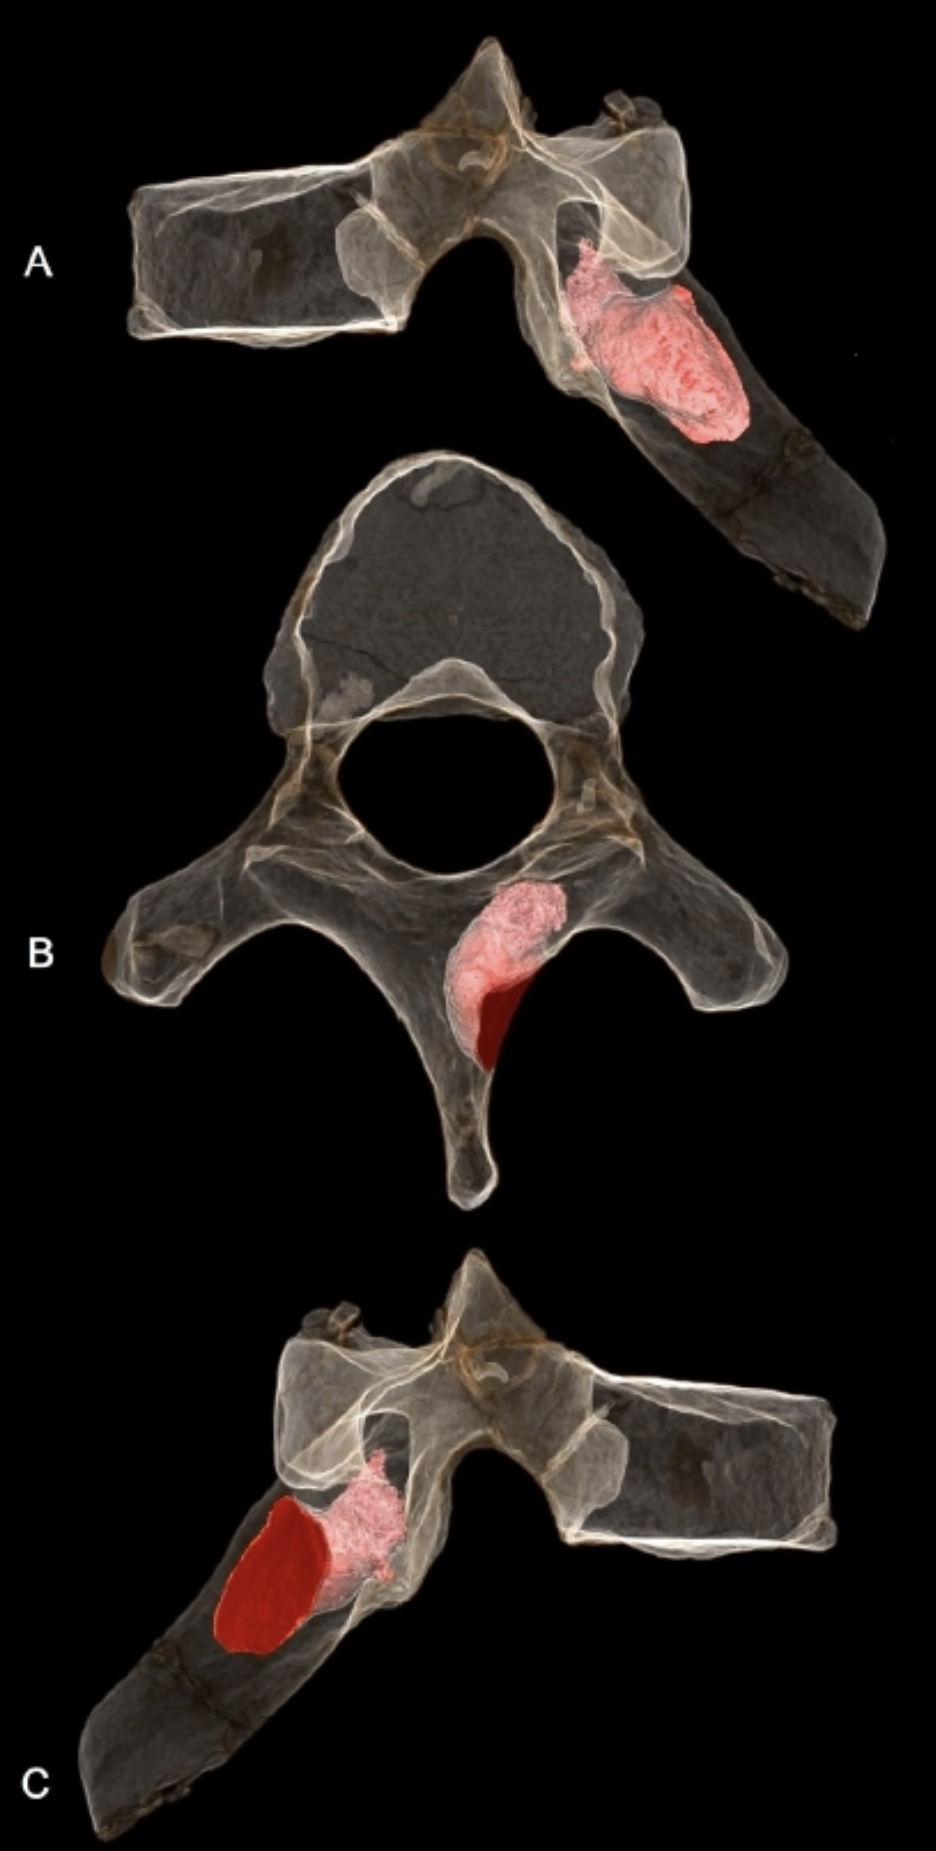

MH1 개체의 여섯 번째 흉추 오른쪽 판에서는 침투성 뼈 종양이 발견되었는데, 이는 아마도 양성 골성 골종으로 추정된다. 이 병변은 6.7mm 깊이로 뼈에 침투해 있었고 너비는 5.9mm였으며, 사망 당시에도 활성 상태였던 것으로 보인다. 종양이 척수관을 관통하지는 않아서 신경학적 합병증을 유발하지는 않았을 것으로 보이며, 척추 측만증(척추의 비정상적인 굽음)의 증거도 없다. 하지만 이 종양은 어깨뼈와 등의 오른쪽 위쪽 사분면 움직임에 영향을 미쳐 급성 또는 만성 통증, 근육 장애 또는 근육 경련을 유발했을 수 있다. ''오스트랄로피테쿠스 세디바''가 나무를 오르는 능력이 필요했을 수 있다는 점을 고려하면, 승모근, 척추기립근, 능형근과 같은 근육들의 부착 지점 근처에 병변이 위치하여 정상적인 움직임 패턴을 제한했을 가능성이 있다. MH1은 인류 화석 기록상 암이 진단된 최초의 사례로, 기존에 가장 오래된 것으로 알려졌던 남아프리카 공화국 스와르트크란스에서 발견된 180만 년에서 160만 년 전의 골육종을 나타내는 SK 7923 중족골 조각보다 최소 20만 년 앞선다. 영장류에서 종양은 일반적으로 발병률이 낮기 때문에 인류 화석 기록에서도 드물게 발견되며, 초기 인류 역시 현대 영장류와 비슷한 발병률을 가졌을 가능성이 높다. 어린 개체였던 MH1에서 뼈 종양이 발견된 것은, 뼈 종양이 주로 젊은 개체에게 발생하는 일반적인 경향과 일치한다.[34]